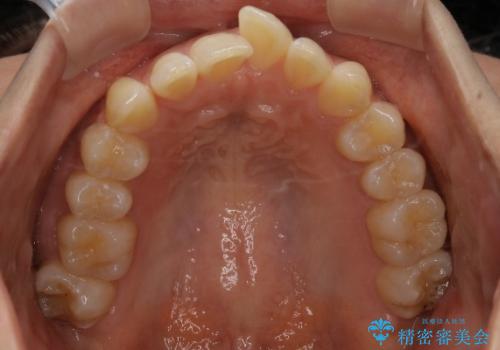

- 審美装置(ブラケット:白/ワイヤー:白)

初診時の歯並びの状態としては、上下ともに前歯部の中等度のがたつきがあり、下の前歯は本来生えるはずの歯が2本生まれつき欠損している状態でした。

また、上顎の歯は虫歯で歯冠が崩壊してしまって保存不可能な歯がありました。

抜歯ありワイヤー矯正にて治療を行い、抜歯する歯に関しては虫歯で抜歯が必要な部分を有効活用することで、健康な歯を保存するように努めました。

見た目、嚙み合わせ及び、治療期間や施術内容に大変ご満足いただきました。